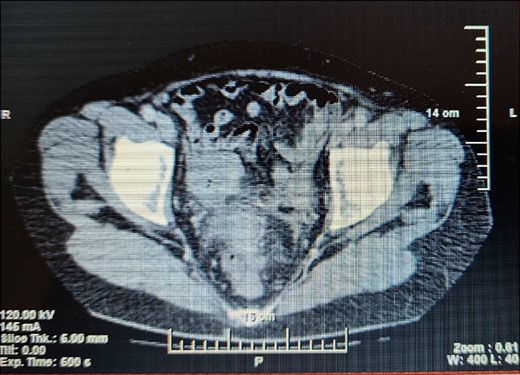

A 63-year- old women was admitted to the surgical department with right abdominal pain radiating to the right inguinal region and low back, and the pain had worsened in the last month. Because of these complains a magnetic resonance imaging was performed on an outpatient basis and a thickening of the sigmoid along a length of ~4 cm was found. The patient tells about a benign education, for which the necessary documentation is missing. Colonoscopy was performed which revealed edema and hyperemia of the mucosa ~20 cm from anorectal line to pseudopolypoid dilated lymphatic vessels as in a malignant process. Three biopsies were performed, the result of which proved the presence of moderately inflamed changes and marked lymphostasis with dilated lymphatics. Given the colonoscopy finding and the inability to rule out a malignant process despite a negative biopsy, a contrast- enhanced computed tomography of the abdomen and pelvis was performed. Examination showed a circumferentially and irregularly thickened intestinal bowel wall up to 15 mm ~ 11 cm from the anorectal line along ~6 cm concentrically stenosing lumen, increasing its density characteristic unevently and mainly on the periphery, compacted perirectal fatty tissue, diverticulosis along the sigmoid course, enlarged, regional lymph nodes up to 14/12 mm (Fig. 1). The blood count showed no abnormalities. Given the suspicions of the presence of a malignant process in the sigmoid, the patient underwent surgery and a thickening was found in the sigmoid area and pericolic adipose tissue with infiltration to the right ovary and right ureter. En block resection of the sigmoid along with the right ovary was performed, which was densely attached to the right ureter. On cutting a macroscopic specimen, the cartilaginous density of the tumor along a length of ~6 cm/d and stenosing the lumen of the intestine was impressed, which confirmed our suspicions of malignancy (Fig. 2). Contrary to our expectations, the histological result proved a complicated colonic diverticulitis with exacerbation, abscessation and spread of the inflammatory process with involvement of the pericolic tissues and right ovary, lymph nodes with mixed reactive lymphadenitis. The patient was followed twice with fibrocolonoscopy and with nuclear magnetic resonance postoperatively, which did not show any pathological changes.

Computed tomography remains the method of choice for the diagnosis of both acute diverticulitis and emerging complications with a sensitivity of 99% [13]. In the two cases describe by Nishiyama et al. [8] the computed tomography shows the thickening of the bowel wall, and the biopsy excludes the presence of malignancy. In the case describe by us, in addition to thickening of the wall over a length of ~6 sm/d, there are also enlarged lymph nodes, as described by Nishiyama [8] in one of the cases. Enlarged lymph nodes rather make the surgeon to think in the direction of the presence of a malignant disease, and this is a serious prerequisite for resorting to surgical treatment. Differentiating malignant from benign disease in the presence of a diverticulum near the tumor suggests complicated diverticular disease, but operative treatment and definitive histological verification are needed because a negative biopsy does not rule out colon cancer.